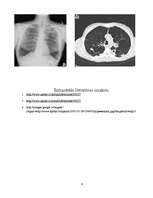

Hroniski obstruktīva plaušu slimība (HOPS)